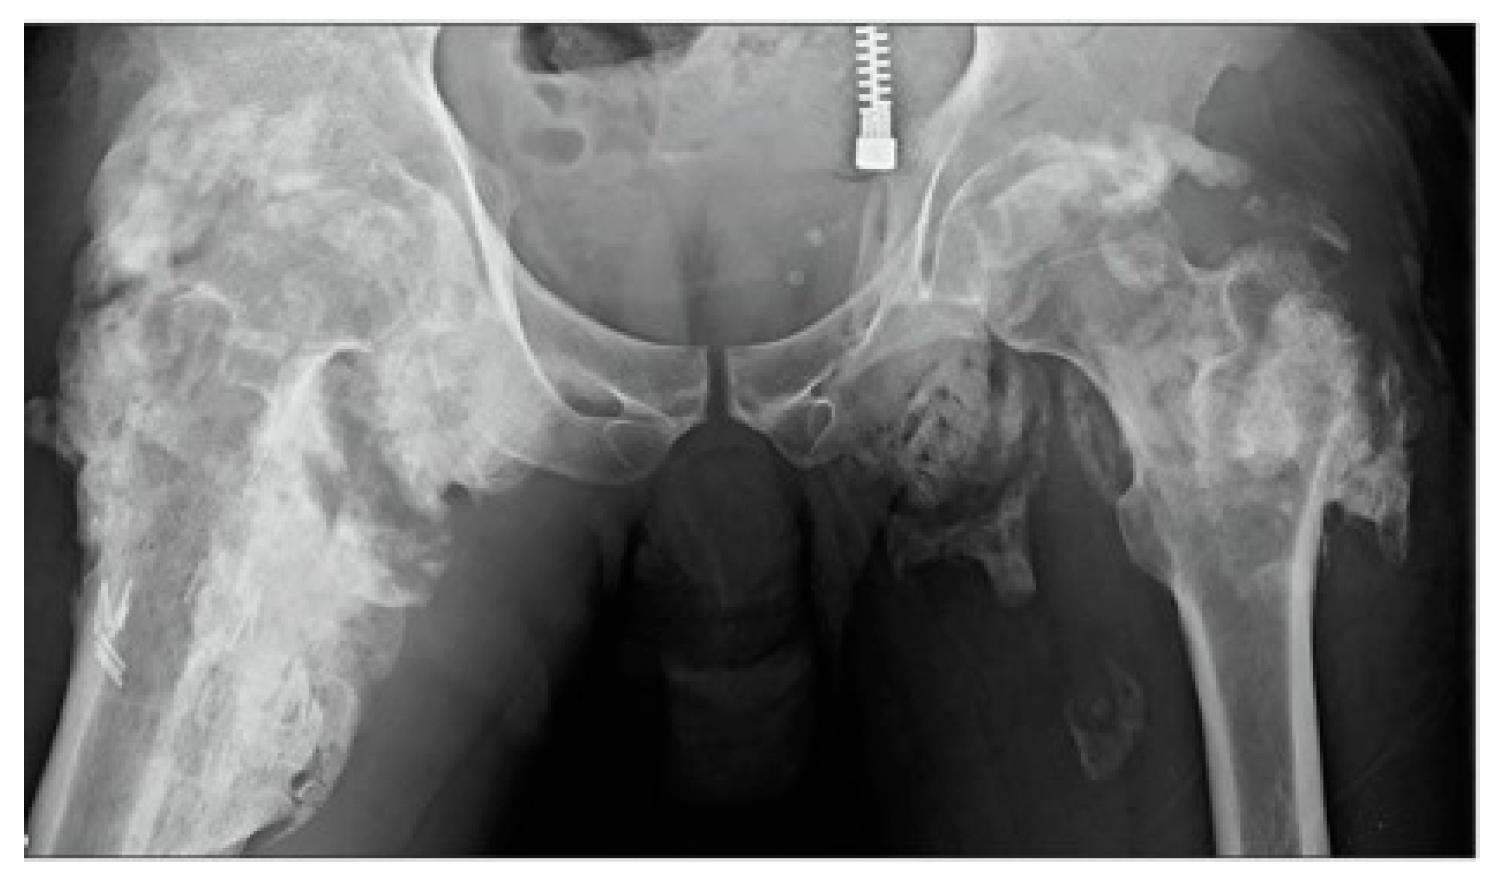

4. Identification and Diagnosis of HO

4.1. Traumatic HO

4.2. Fibrodysplasia Ossificans Progessiva (FOP)